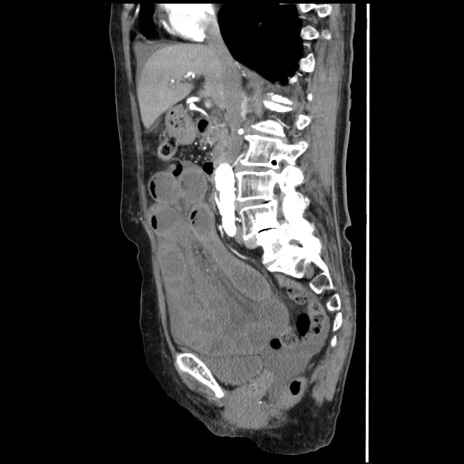

症例1(矢状断像)

【症例】80歳代女性

【主訴】腹痛

【現病歴】8時間前から腹痛あり来院。

【既往歴】糖尿病、脂質異常症、子宮体癌にて子宮全摘術

【身体所見】意識清明・会話良好だが腹痛で苦悶様、全腹部にわたって反跳痛と圧痛あり

【データ】WBC 13600、CRP 0.14、LDH 224、CK 90